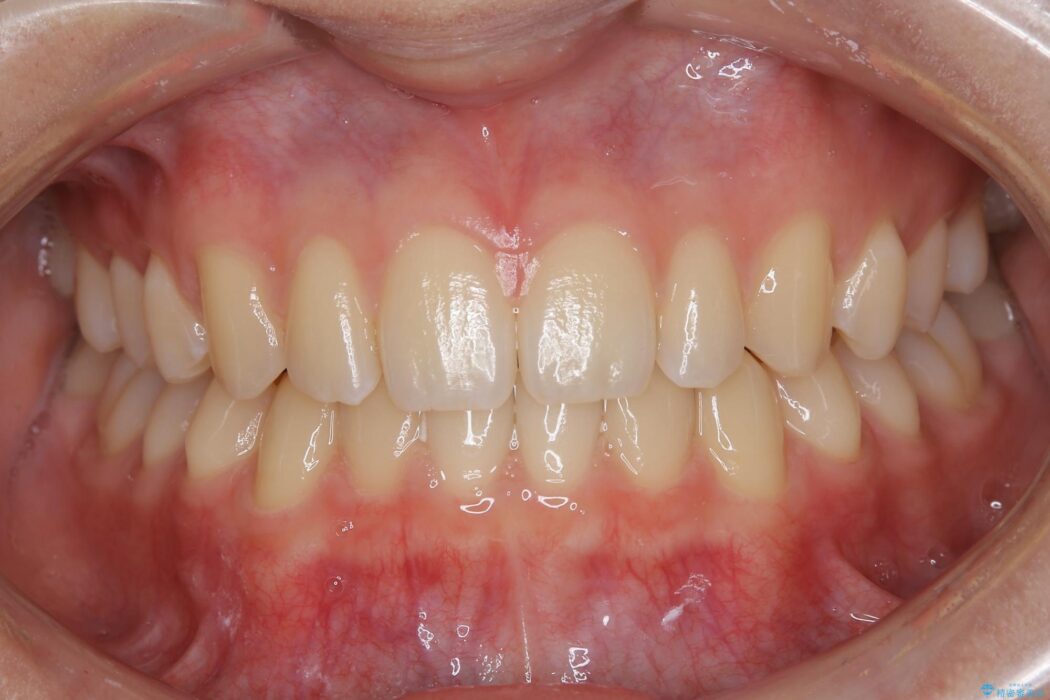

すきっ歯を改善したいとご来院された患者様です。

インビザライン・クリンチェック(シミュレーション)を行い、インビザラインライトで治せる範囲であると診断し、矯正治療を行いました。

マウスピース14枚・期間4ヶ月で主訴であるすきっ歯を改善し、治療を終えることが出来ました。